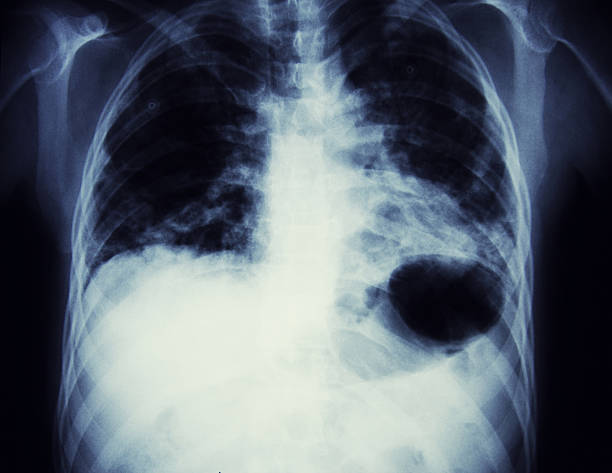

폐암은 초기에는 증상이 미미하거나 없을 수 있습니다. 그러나 조기에 발견하고 진단받으면 치료의 성공률이 훨씬 높아집니다. 초기에 폐암을 발견하면 조기 치료를 시작하여 종양의 성장과 전이를 제한할 수 있습니다. 뿐만 아니라, 치료에 있어 다양한 치료 방법을 활용할 수 있어 폐암 초기 증상을 잘 알고 있는 것이 중요합니다.